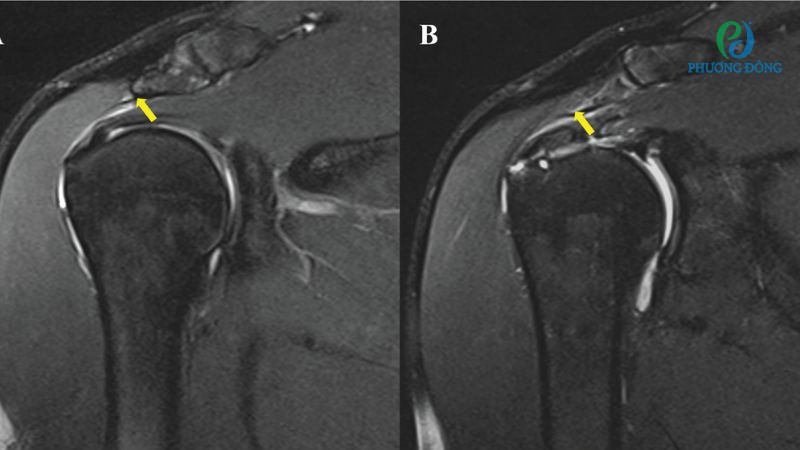

Dựa vào bước thăm khám lâm sàng tình trạng bệnh nhân ban đầu, bác sĩ sẽ đưa chỉ định xét nghiệm chuyên sâu hơn để tìm nguyên nhân và đánh giá mức độ tổn thương ở khớp vai. Cụ thể như sau:

- Chụp X-quang kiểm tra các tổn thương xương ở khớp vai.

- Chụp MRI, siêu âm đối với những nghi ngờ chấn thương mô mềm như dây chằng, gân, cơ xung quanh khớp vai.

- Chụp CT cung cấp hình ảnh chi tiết, rõ nét hơn với những tổn thương xương vùng khớp vai.